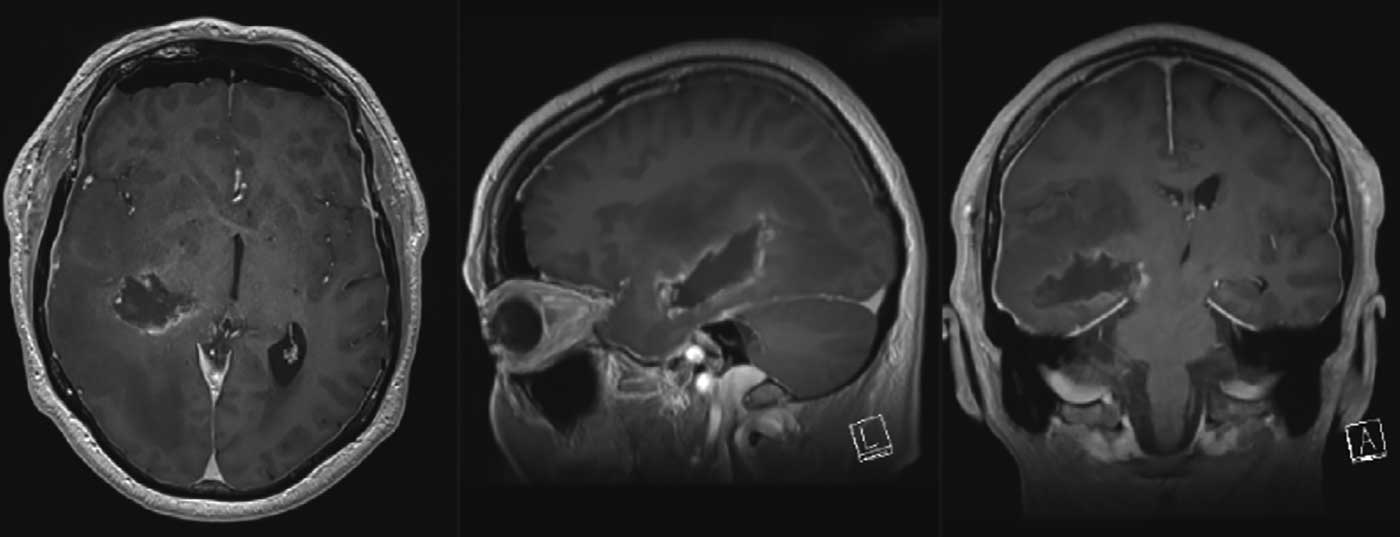

Fallbericht: Der 56-jährige Patient litt seit drei Monaten unter Kopfschmerzen und Übelkeit sowie unter einer zunehmenden psychomotorischen Verlangsamung. Klinisch präsentierte er eine Mundastschwäche des linken N. facialis, eine armbetonte milde Hemiparese links und einen Neglect nach links. Ein Singultus wurde als Zeichen eines erhöhten Hirndrucks gesehen. Durch den Hausarzt wurde eine bildgebende Abklärung initiiert, bei der sich eine grosse rechts-temporale Raumforderung präsentierte.